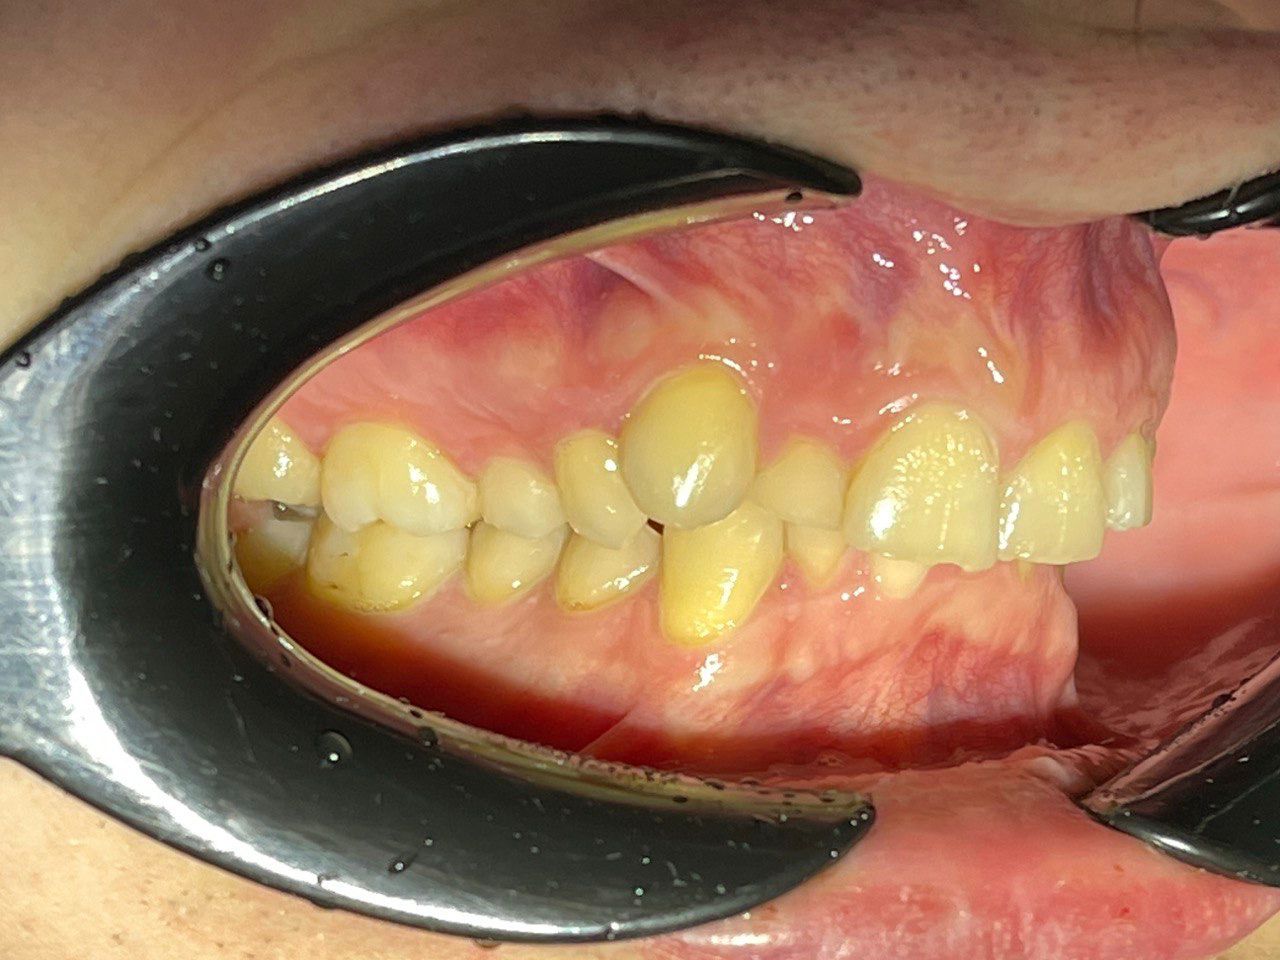

Выявленные проблемы

• Мезиальная окклюзия

• Периодонтит зуба 4.6.

• Дистализация нижнего зубного ряда с опорой на ортовинт

Брекет-система Q